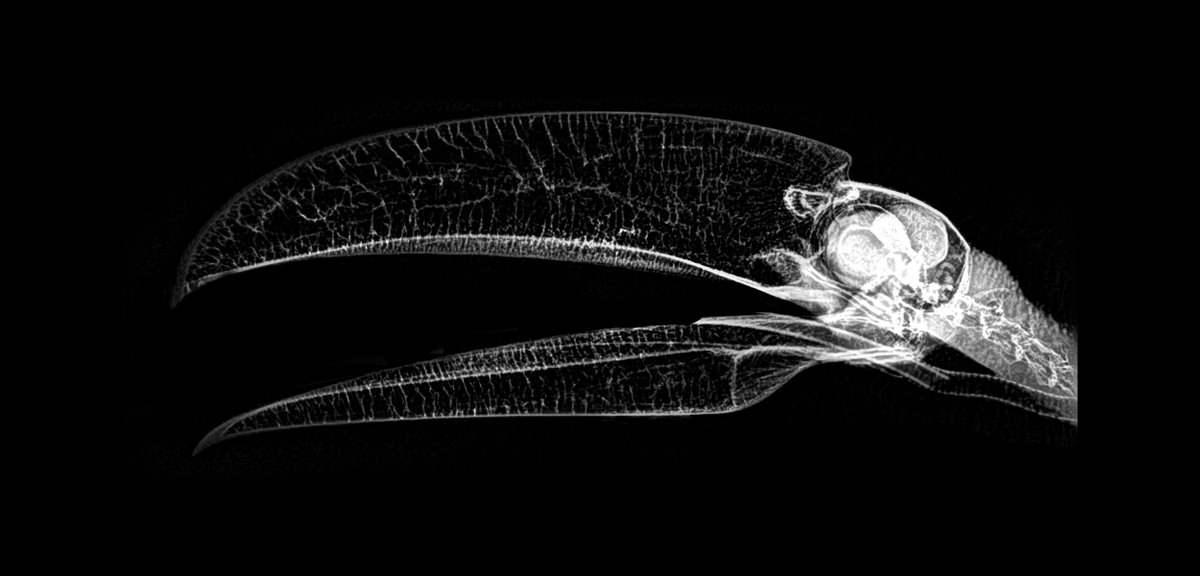

Tucán